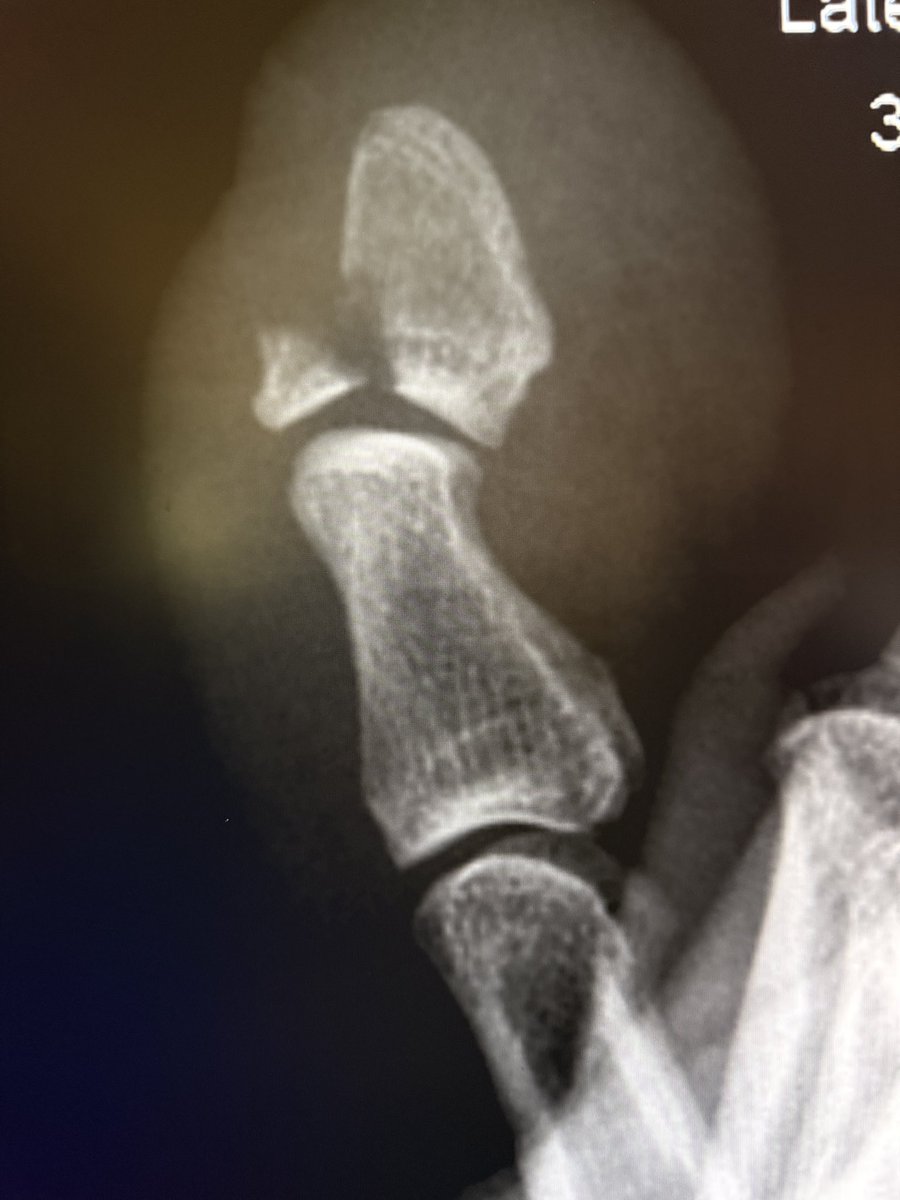

Nothing fancy today! This is just a classic case with an elevated posterior fat pad (also called the “posterior fat pad sign”) on an elbow X-ray, with an ultrasound to back it up. —Classic signs in radiology from my reporting list

Nothing fancy today!

This is just a classic case with an elevated posterior fat pad (also called the “posterior fat pad sign”) on an elbow X-ray, with an ultrasound to back it up.

—Classic signs in radiology from my reporting list